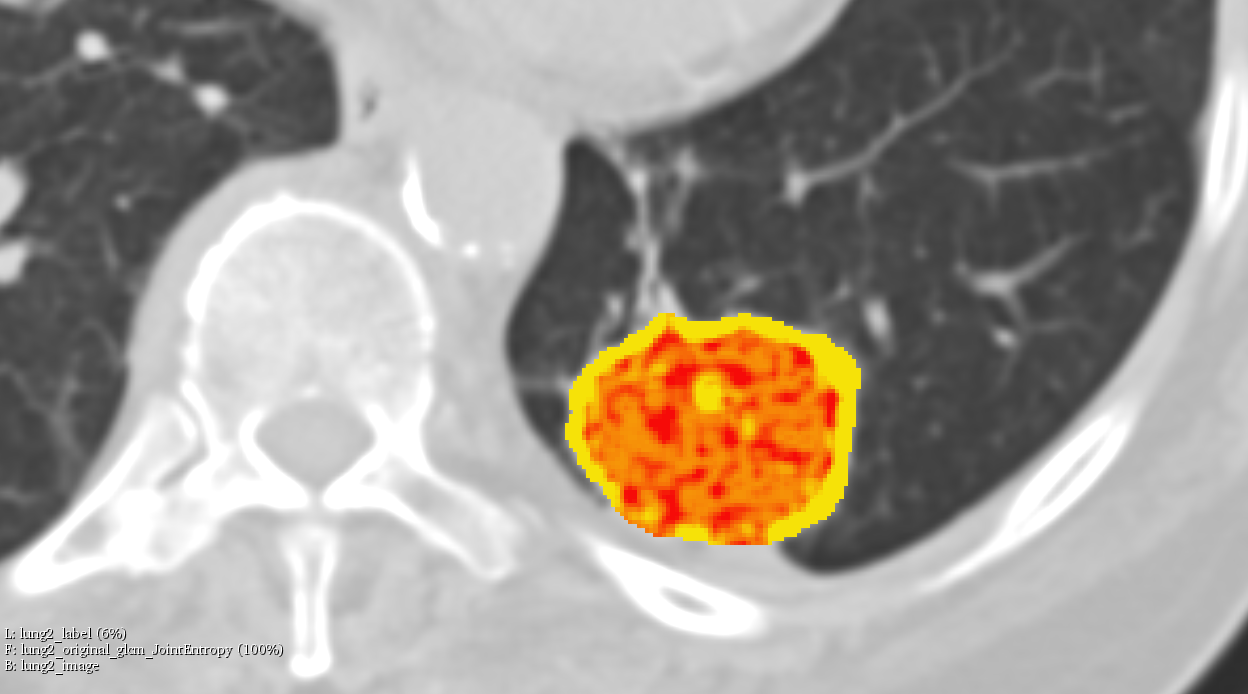

Illustrations

Objective #2